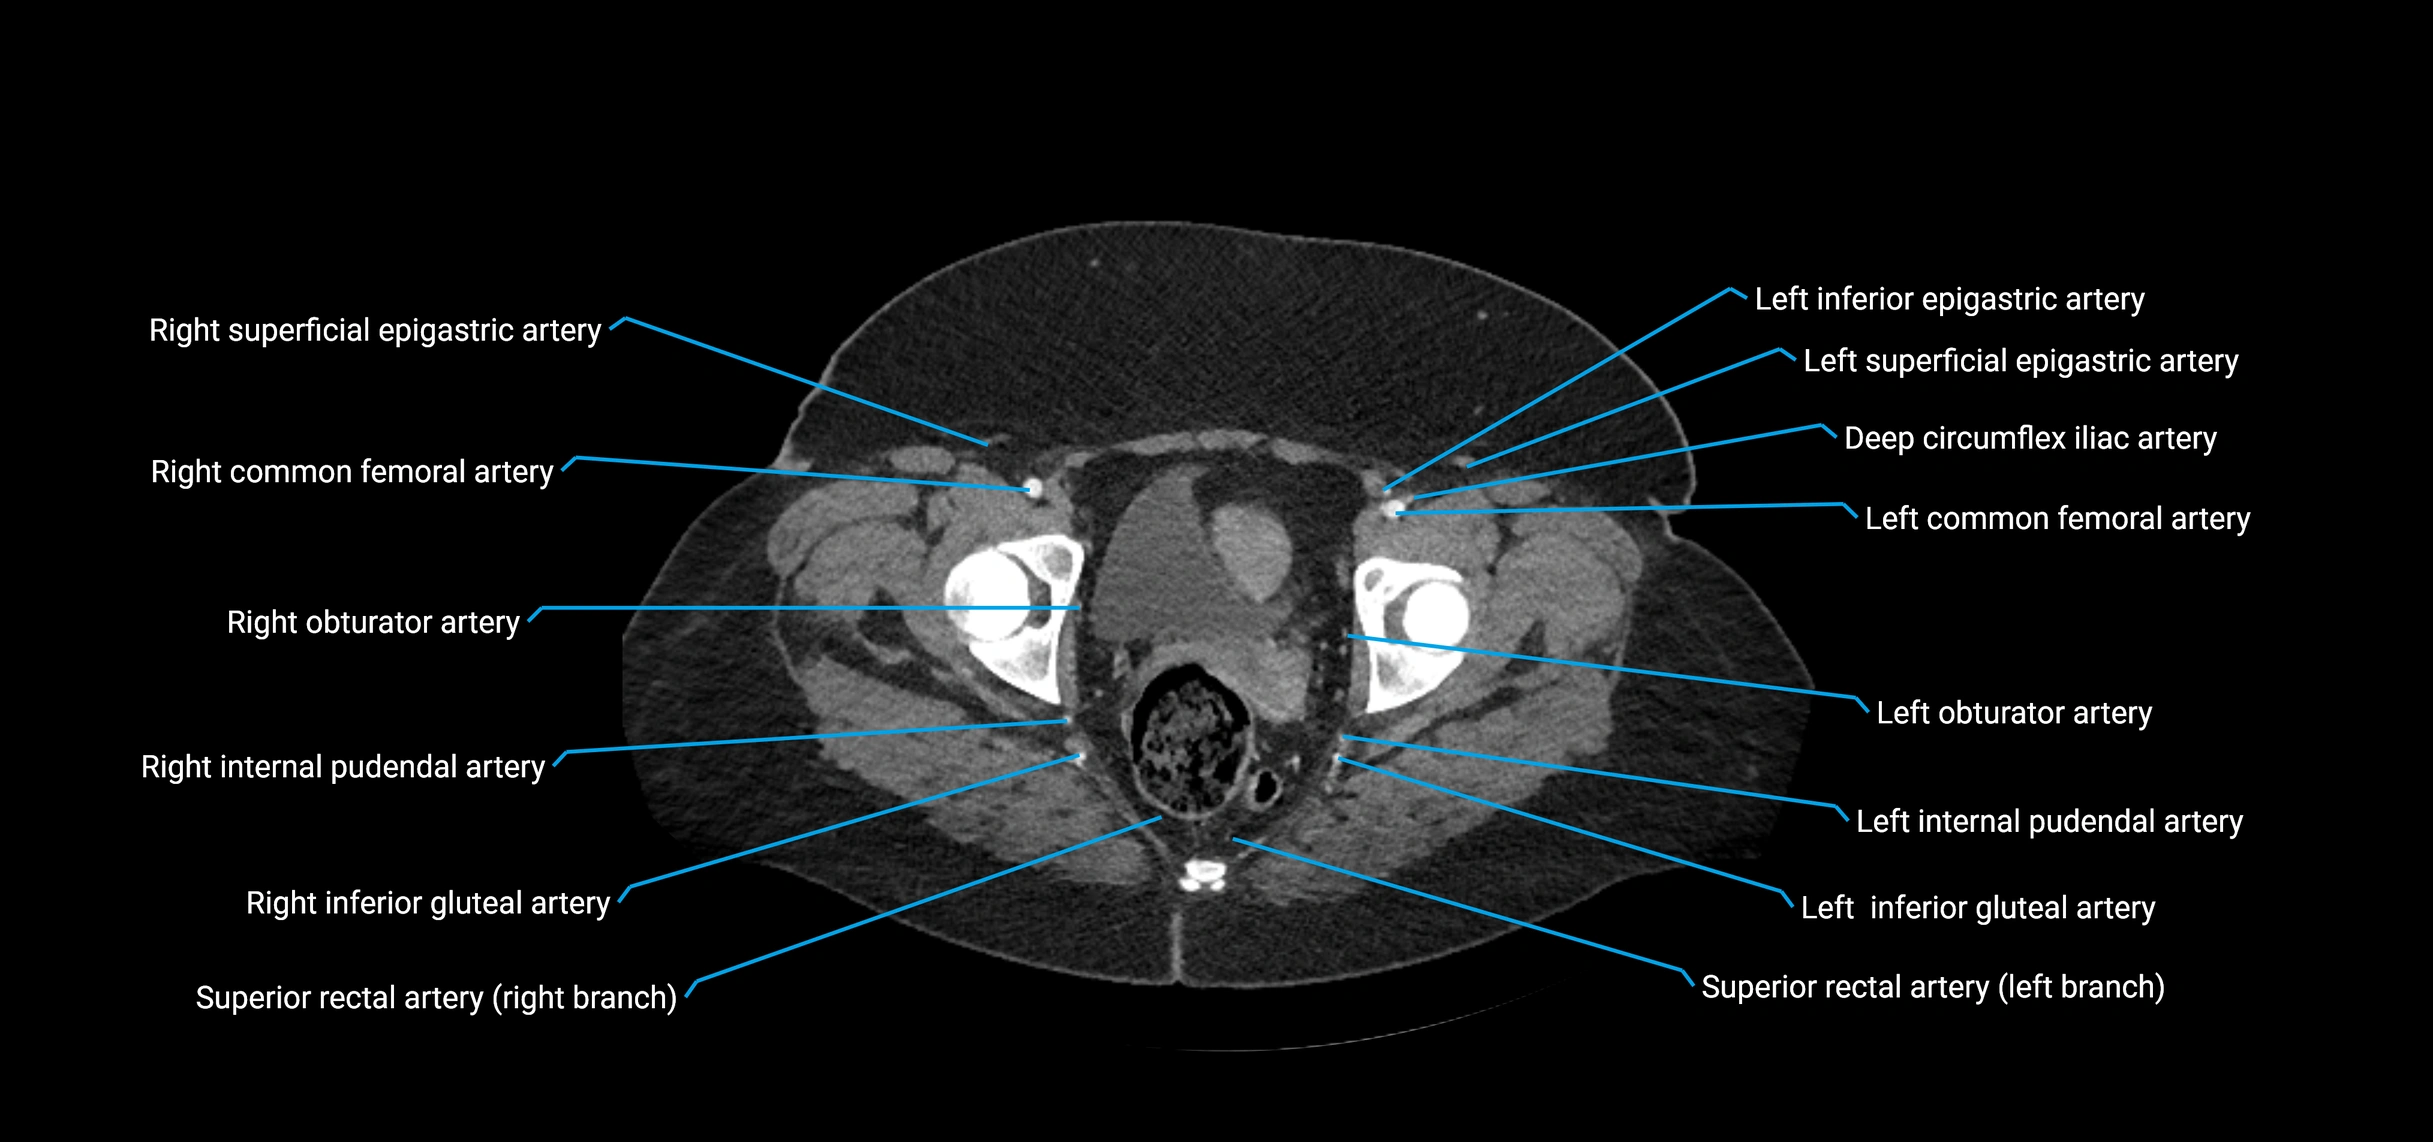

Contrast-enhanced CT (CTA):

• Gold standard for abdominal aortic imaging

• Provides excellent detail of lumen, wall, aneurysm, thrombus, and branch vessels

• Multiplanar and 3D reconstructions help in aneurysm measurement, stent graft planning, and dissection evaluation

• Detects acute rupture, traumatic injury, or occlusion with high sensitivity